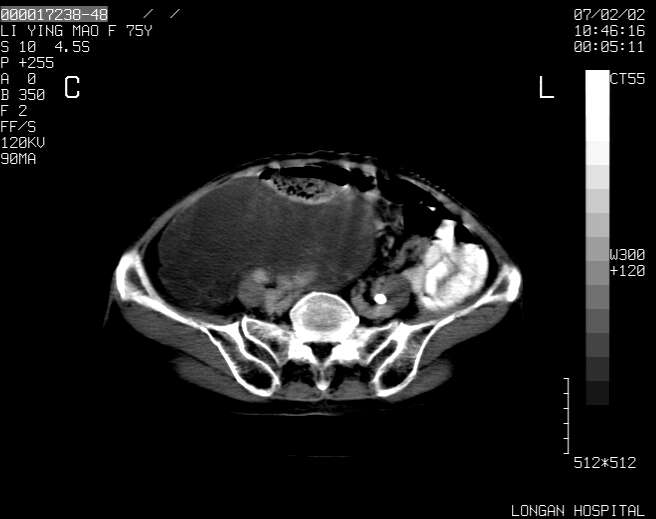

以下是引用dyqct在2007-2-10 8:53:00的发言:[br]考虑:1、肝脏多发囊肿[br] 2、左肾囊肿,右肾多发结石并积水。[br] 3、右胸少量积液。[br] 4、右肾周包裹性积液或淋巴管瘤(有见缝就钻的征象、薄隔、小结节状钙化)?[br] 5、腰椎动脉瘤样骨囊肿?[br] [br] [br]